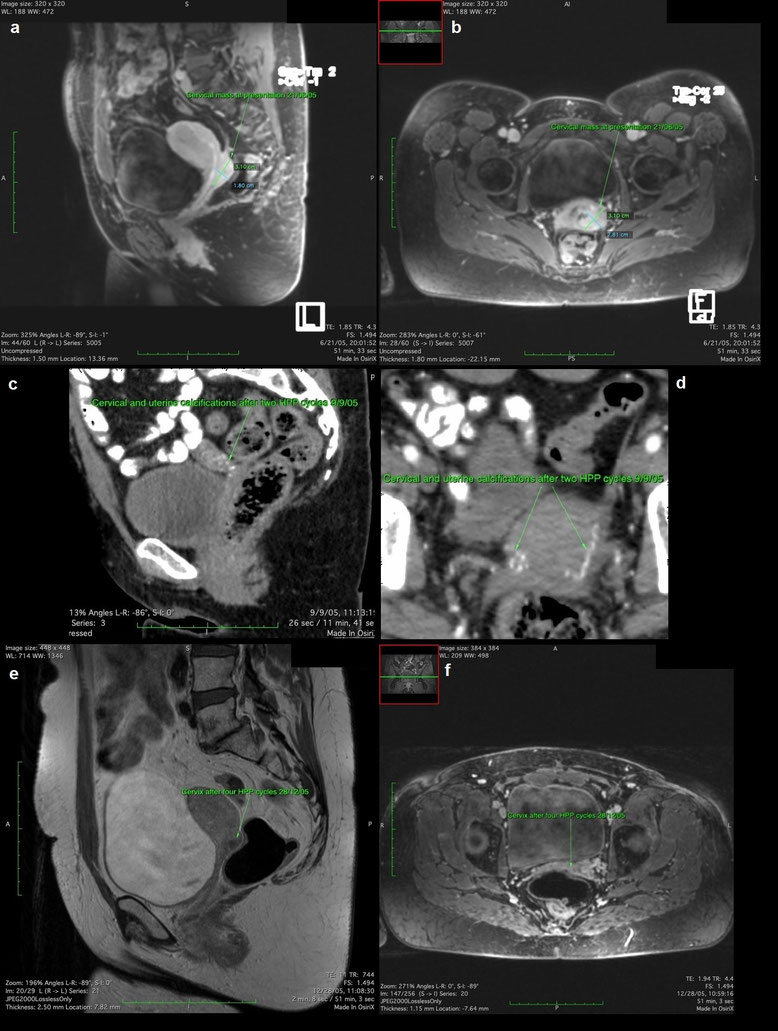

Die Patientin erhielt im Mai 2005 zwei Behandlungszyklen mit Carboplatin und Taxol. Ein MRT des Abdomens und des Beckens im Juni 2005 zeigte eine 3,1 x 1,8 x 2,8 cm große Raumforderung, die das dorsale Vaginalgewölbe, die rechte Plica rectouterina bis in das Rektum und präsakrale Weichteile links infiltrierte. Die Patientin lehnte eine Radiochemotherapie ab.

Ein CT des Abdomens und Beckens vom September 2005 nach zwei HPP-Zyklen zeigte ausgedehnte Verkalkungen in der Zervix und im Uterus. Nach zwei weiteren HPP-Zyklen zeigte ein MRT des Abdomens und des Beckens im Dezember 2005, eine nekrotische Resttumormasse im Gebärmutterhals.

Im Februar 2006 führten wir eine radikale Hysterektomie durch, die das vollständige pathologische Ansprechen bestätigte. Die Patientin erhielt einen adjuvanten HPP-Zyklus mit 50 mg Cisplatin, 30 mg Adriamycin und 30 mg Mitoxantron. Die Patientin wurde einmal jährlich mittels MRT kontrolliert. Diese ergaben keine Anzeichen eines Rezidivs. Die Patientin ist seit 15 Jahren tumorfrei bei sehr guter Lebensqualität.

Mehrere MRT- und CT-Aufnahmen einer Patientin mit fortgeschrittenem Zervixkarzinom vor und nach Behandlung mit mehreren HPP-Zyklen, dokumentierend die Tumorverkalkung, Tumornekrose und Therapieansprechen.